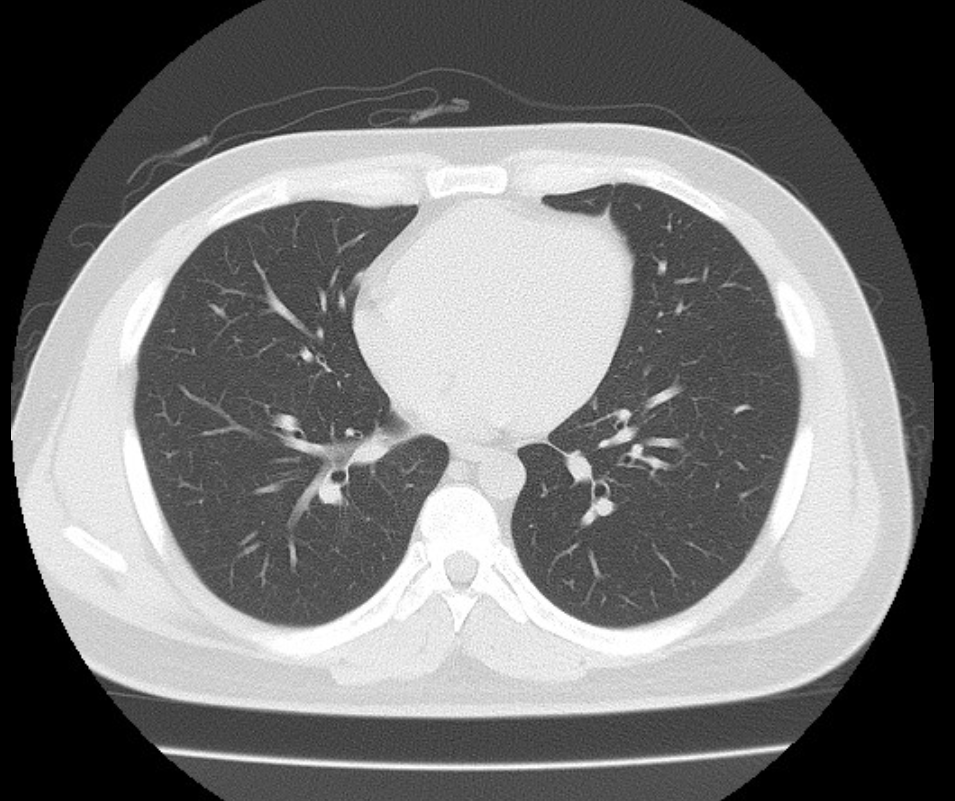

폐ct사진 받았는데 엄청 많더라구요.. 우중엽(40#)에 부분고형결절(6mm, 고형 2mm)결절이 있다고 소견을 받았는데 아래 ct사진 상 위험한 결절로 보이는지 판독좀 부탁드리겠습니다 ㅜㅜ. 다른 사진들 더 많지만 앞뒤 전후로 몇장씩만 가져왔어요..

• 3번 째 사진

밑에서 3번째 사진 우중엽 (보이기로는 왼쪽에 있는게 오른쪽 폐입니다)

흐릿하게 보이는 병변이네요

일반적으로 간유리음영과 결절이 같이 있을때 6mm 이상이면 암일확률이 1~2% 된다고 합니다. 저같으면 6개월후 추적검사를 해볼거 같네요